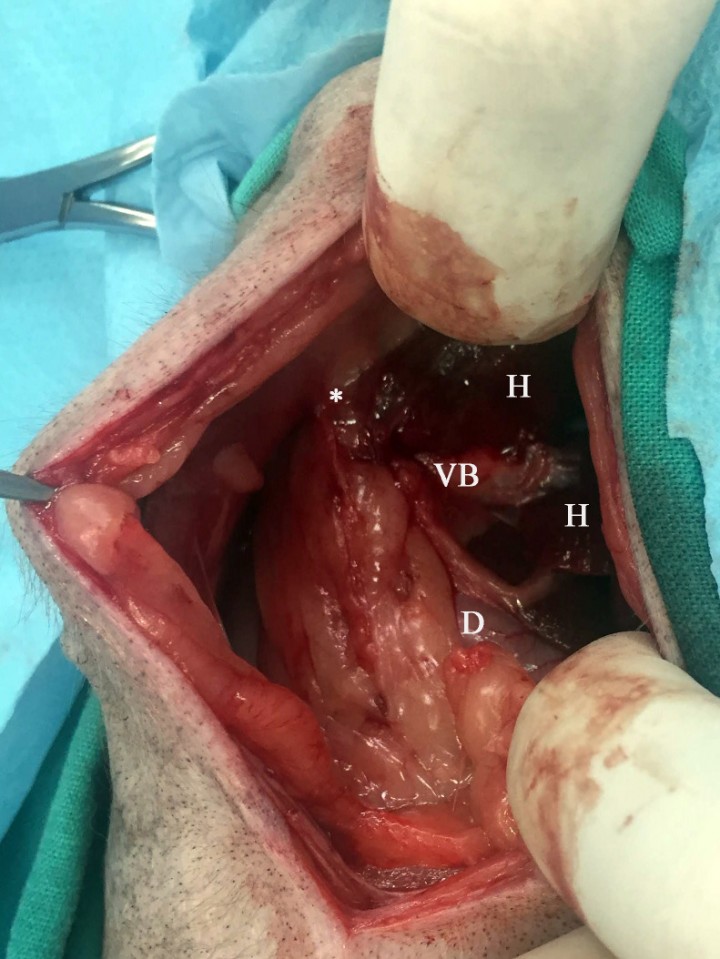

Se planificó la realización de una laparotomía exploratoria media craneal, para la que se estableció el protocolo anestésico y analgésico indicado en la Tabla 1. Durante la cirugía se localizó la vesícula biliar en su posición anatómica, aunque tenía un aspecto rojo marronáceo y consistencia endurecida, con intensas adherencias al lóbulo hepático adyacente, la pared abdominal derecha y la serosa del duodeno proximal (Fig. 6). Tras la liberación de la vesícula biliar mediante disección roma de todas estas adherencias, se realizó una colecistectomía. Tras la intervención, al incidir la vesícula biliar, se observó un marcado engrosamiento de su pared y presencia de varios cálculos biliares (Fig. 7).

<p>Imagen durante la cirugía del Caso 2, en la que al localizar la zona de la vesícula biliar (VB), no es posible distinguirla debido a las adherencias que presenta a la pared abdominal craneal (asterisco), duodeno (D) y parénquima hepático (H).</p>

Imagen durante la cirugía del Caso 2, en la que al localizar la zona de la vesícula biliar (VB), no es posible distinguirla debido a las adherencias que presenta a la pared abdominal craneal (asterisco), duodeno (D) y parénquima hepático (H).